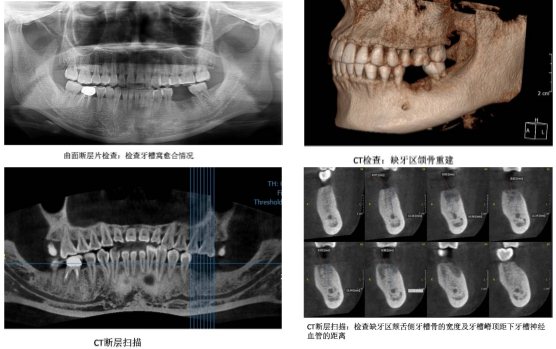

1、术前检查:术前检查包括全身情况检查:如血常规、血糖、血清术前八项、凝血四项等。局部检查包括曲面断层片、CT的检查。